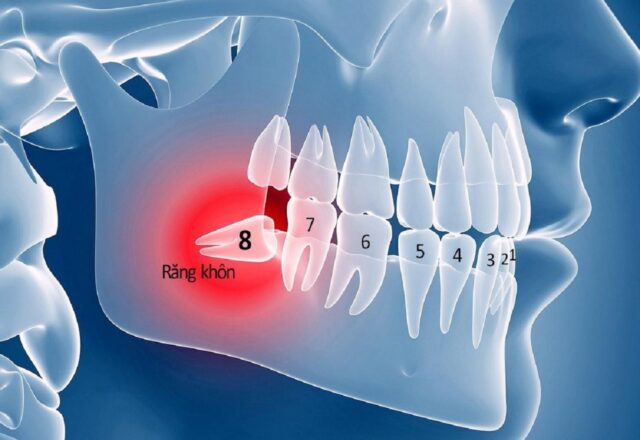

Răng khôn là chiếc răng cuối cùng mọc trên cung hàm của mỗi người. Chúng nằm ở vị trí trong cùng, sau răng số 7 (răng hàm lớn thứ hai).

• Thời điểm mọc: Răng số 8 thường xuất hiện trong độ tuổi từ 17 đến 25, giai đoạn con người đã trưởng thành và được xem là “khôn” hơn, do đó mới có tên gọi là răng khôn.

Vị trí mọc của răng số 8

• Sự cản trở từ răng số 7: Răng 8 mọc ngầm thường gặp sự cản trở từ chân hoặc thân răng số 7 ở phía trước, khiến nó không thể trồi lên đúng vị trí thẳng đứng.